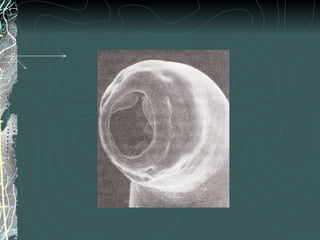

Nemátode de mayor tamaño

Blanco o rosado nacarado

Extremos ahusados

Boca triangular con 3 labios

carnosos y dentados